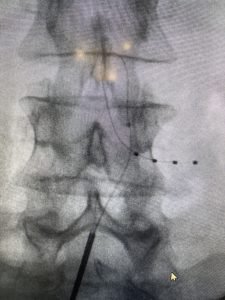

A neuromodulação envolve o implante de pequenos eletrodos para estimular áreas específicas do cérebro, da medula ou dos nervos responsáveis pelo processamento da dor. A estimulação pode ajudar a reduzir a intensidade da dor ou até mesmo suprimir completamente.

Existem alguns métodos de realização da neuromodulação invasiva. As mais comumente utilizadas são: a estimulação elétrica periférica (PNS), a estimulação medular, a estimulação do gânglio da raiz dorsal e a estimulação cerebral profunda. Cada método é selecionado com base nas necessidades individuais do paciente e na natureza da dor.